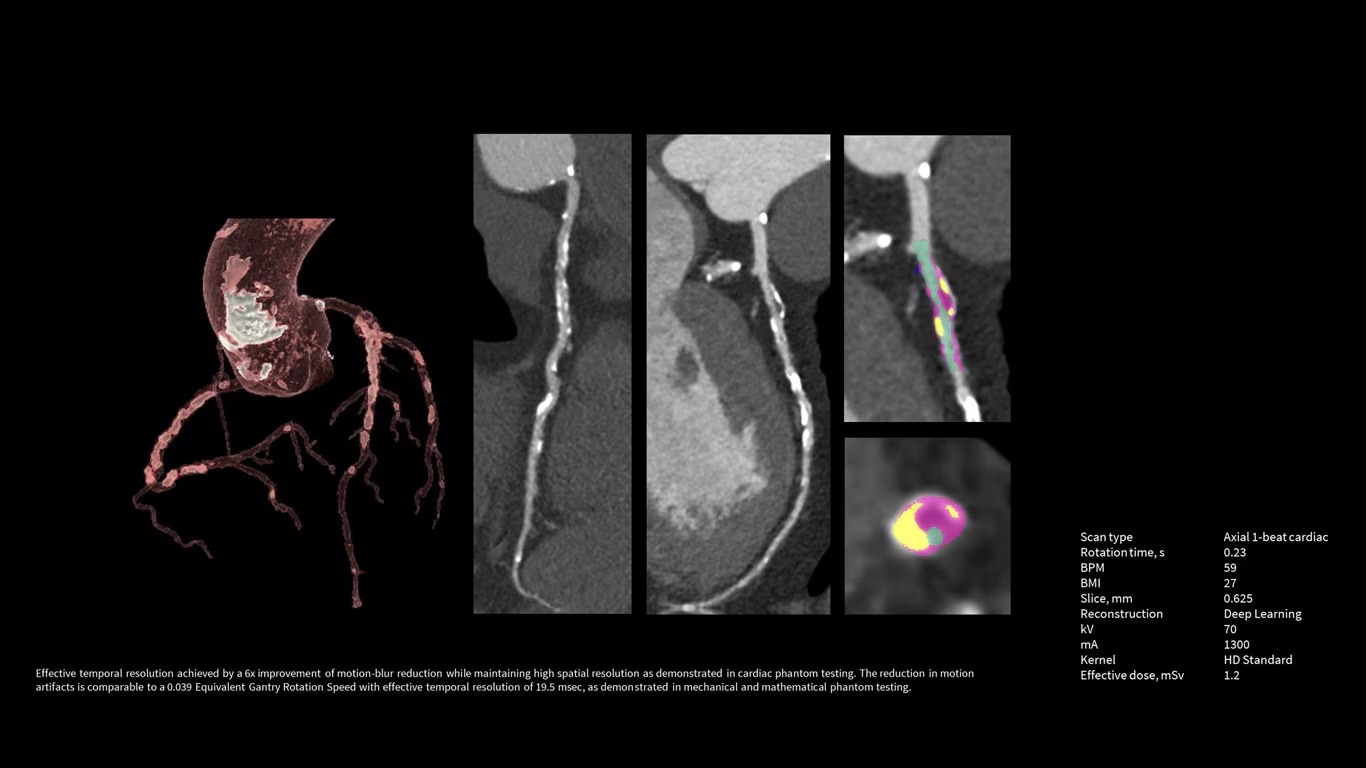

Upgrade to the industry's fastest rotation time

The Revolution Apex platform allows you to upgrade your gantry rotation speed. You can start with 0.28 sec gantry rotation time, and at any point in time when you need to advance your cardiac capability, you can upgrade to 0.23 seconds per rotation with the industry’s fastest rotation time.

Power like never before

The Revolution Apex platform provides high power output. The ability to upgrade means that siting challenges no longer prevent you from high power output to your department. If your siting power is limited to 150 KVA in the initial installation, you can start with the Power Pro option at maximum 1200 mA, and later on, you can scale up to 1300 mA Power Xtream when you upgrade the powerline.